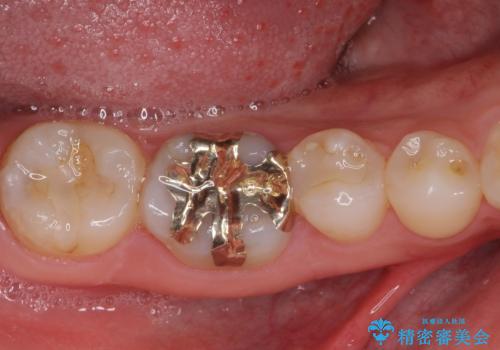

当初はセラミックインレーによる修復治療を希望されいましたが、カウンセリングの結果、審美性よりも安定性を優先され、PGAインレー(ゴールドインレー・白金加金合金インレー)による治療を行うこととしました。

仮詰め材を外すと虫歯が残っていたので、全てを取り除いた後に、ゴールドインレーの型どりを行いました。

ゴールドインレーをご自身で選択いただいたものの、どういった仕上がりとなるか不安を感じていたようですが、実際に装着された口腔内をご覧になり、思ったほど金属色が気にならないとのことでした。

咬んだ感触はご自分の歯のときと比べ全く遜色なく、患者様には大変満足していただきました。